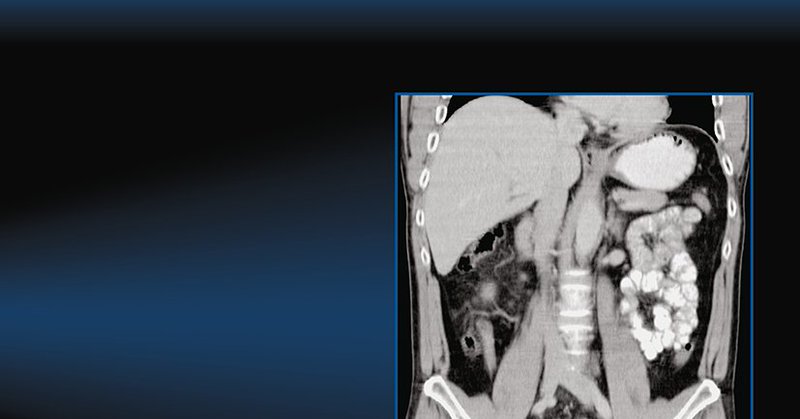

During hepatocarcinogenesis, changes in vascularity can be sensitively depicted with dynamic contrast-enhanced US and categorized using CEUS LI-RADS. Learn more in this new article, and don't miss the accompanying videos! https://t.co/z02nzn4076

@BubbleDocSteph @BubbleTechChris

Check out our paper published online! 2023 Oct 7. @Abdominal_Rad Radiol (NY) doi: 10.1007/s00261-023-04031-8 Unique portal venous phase imaging discordance between #CEUS and #MRI: a valuable predictor of intrahepatic cholangiocarcinoma #radiology #ultrasound @icus_society

At Last!! Now published in #hepatology. Our multicenter #CEUS @LIRADS5 study. 95% specificity for LR-5 lesions!!! @sruradiology #ultrasound #radiology @icus_society @drdavidburrowes #MRI #contrastultrasound @ayakamaya